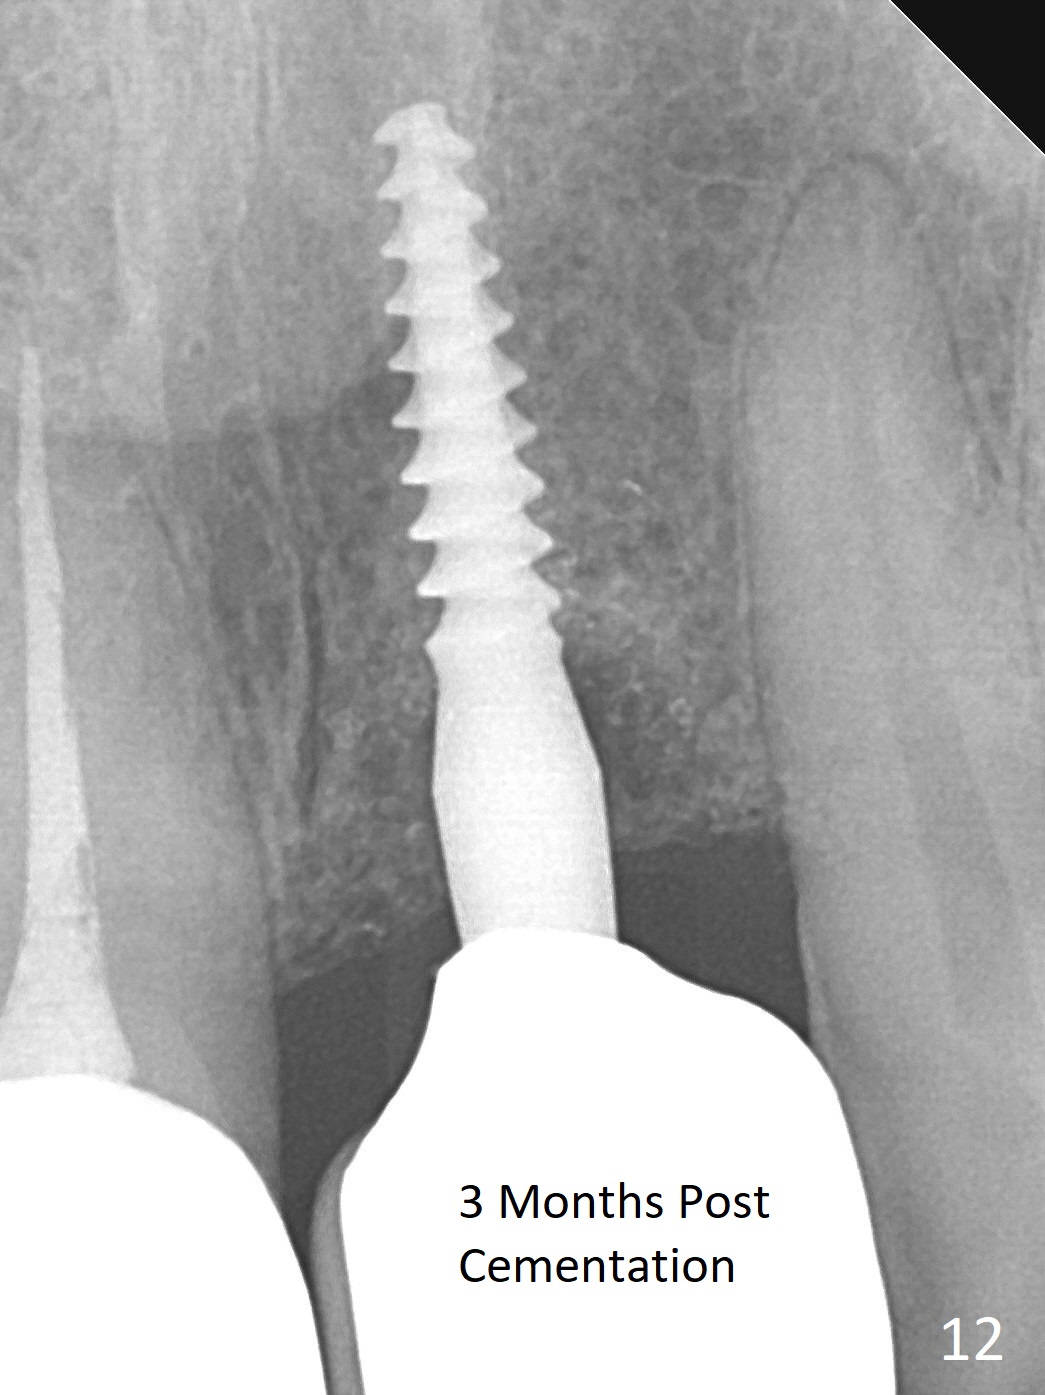

Three months postop there is no gross bone loss around the implant (Fig.10). It remains the same 5 months postop (immediately post cementation, Fig.11) and 3, 11 months post cementation (Fig.12,13).